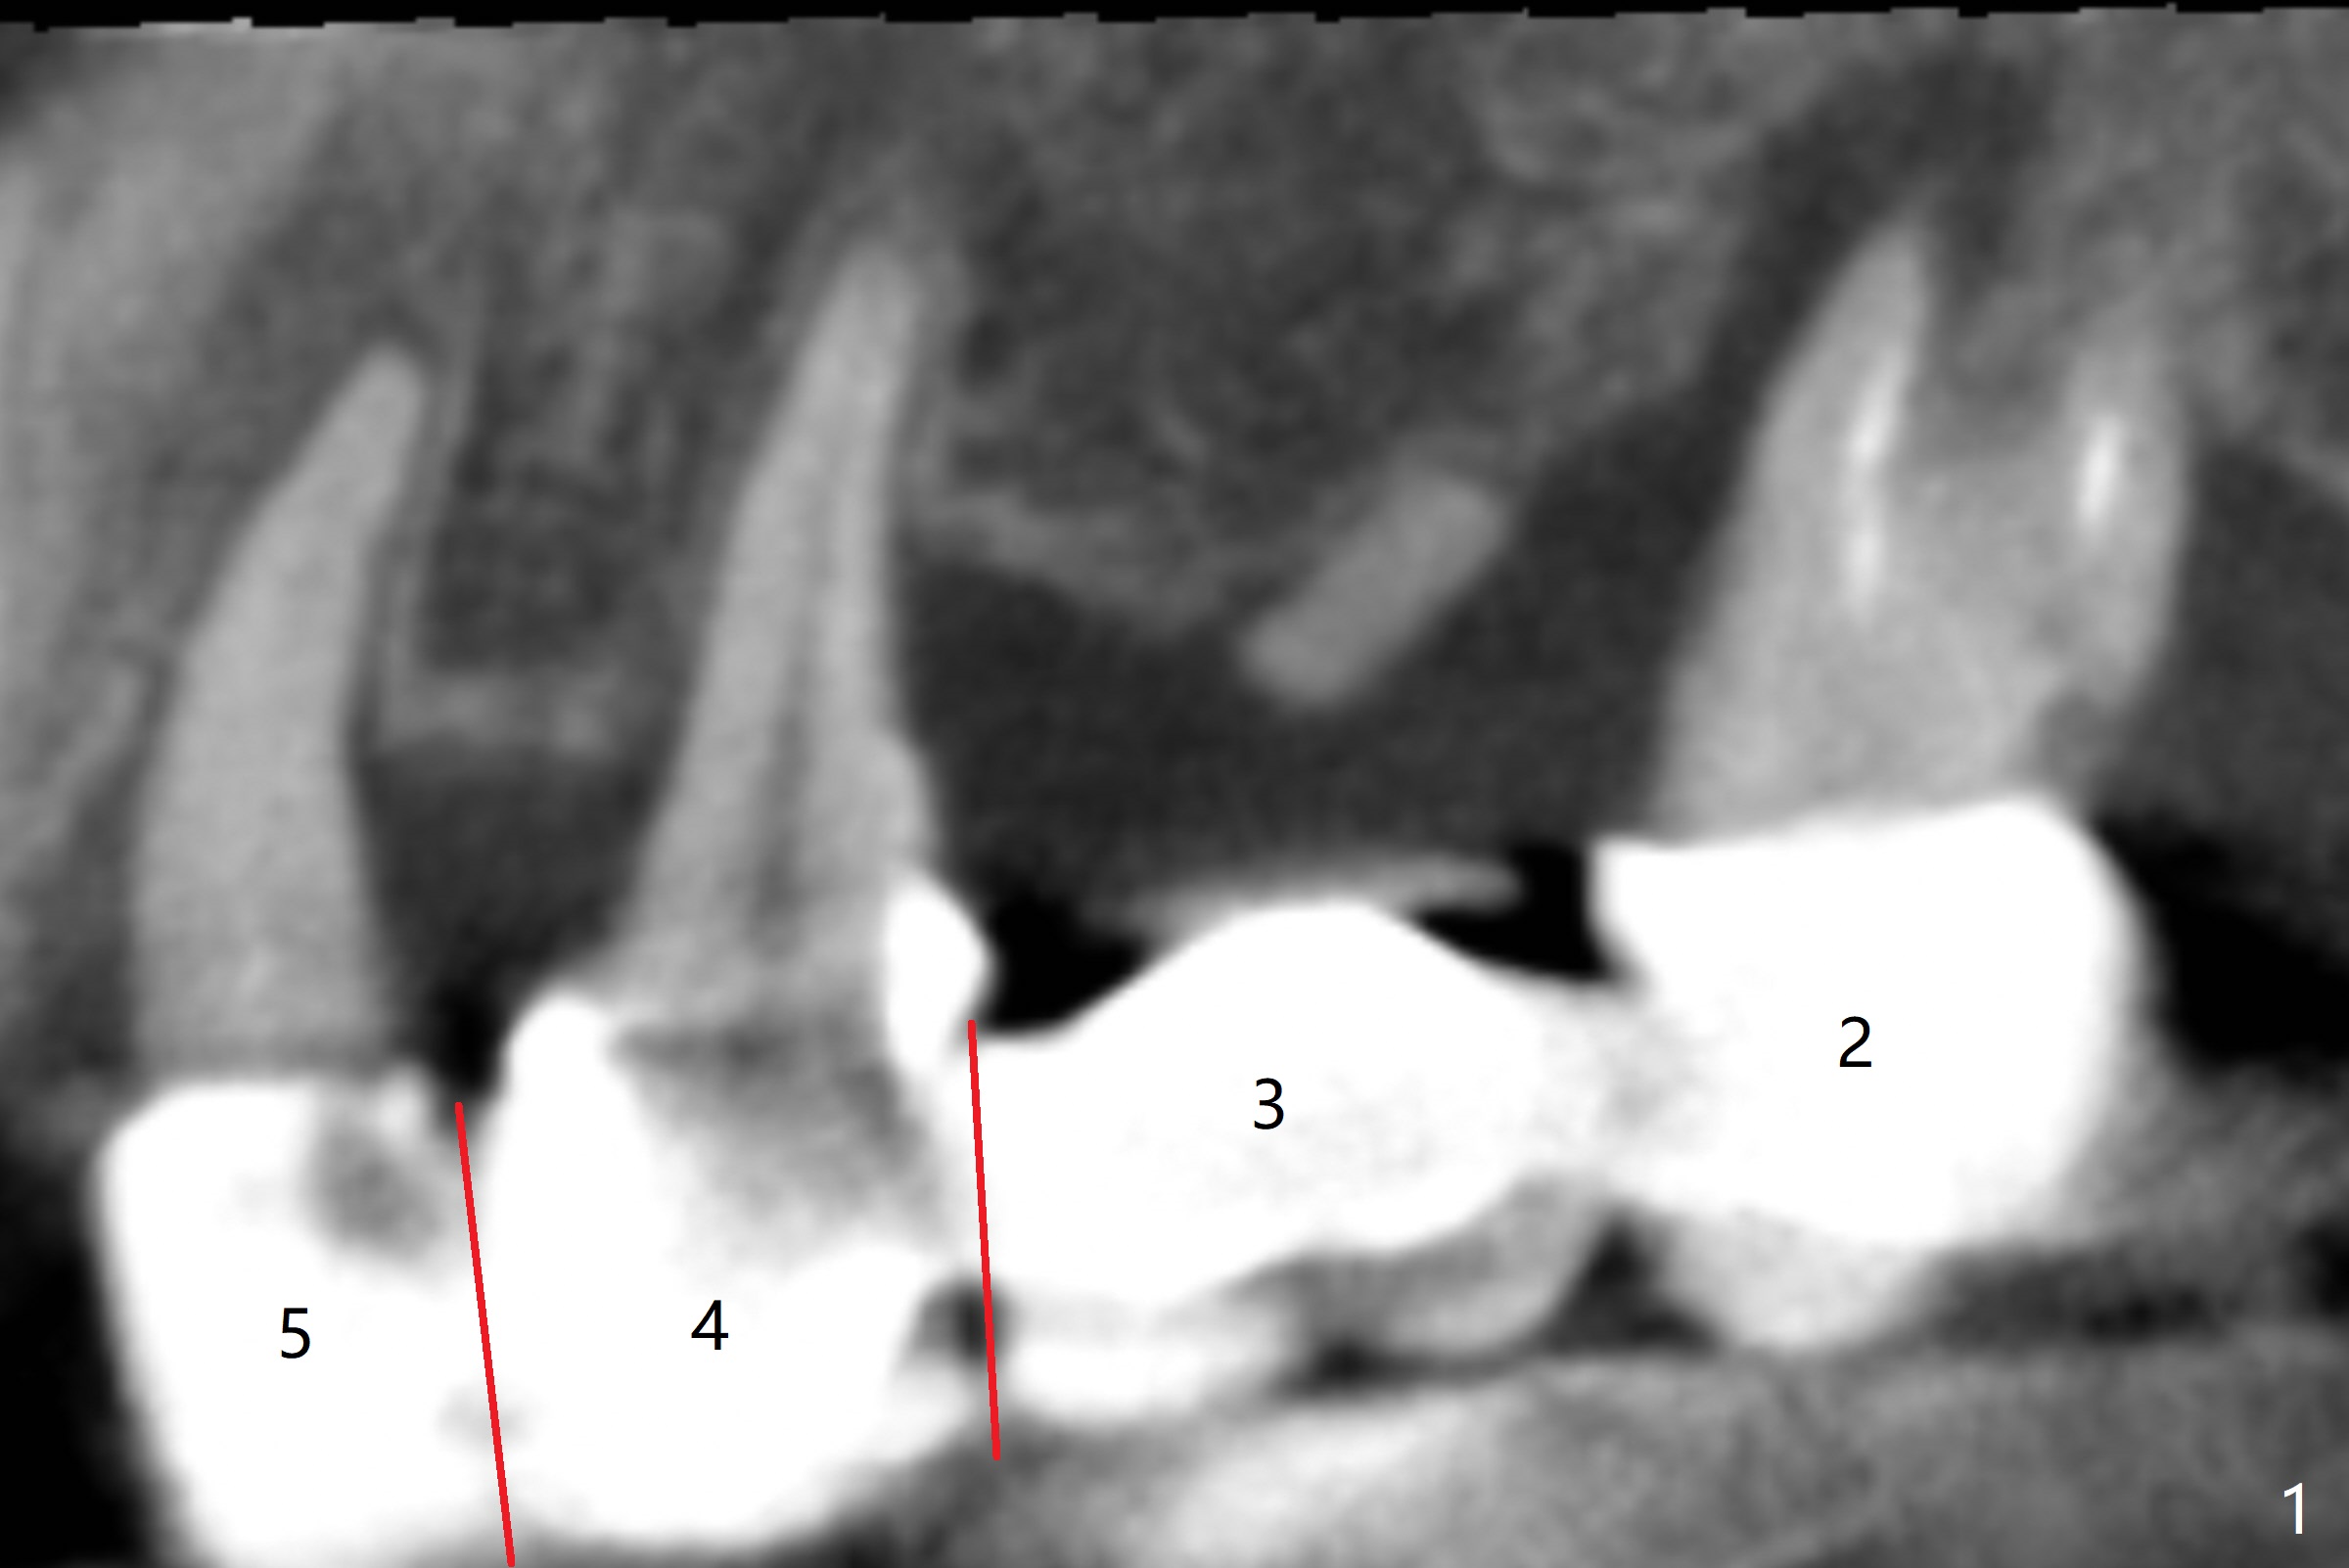

A 43-year-old woman has a failing upper right bridge (Fig.1: #2-5). While the abutment at #5 has apparently palatal open margin (Fig.2,3) and that at #4 has severe palatal bone loss (Fig.4 arrow), that at #2 has the poorest prognosis (Fig.6,7). Panoramic X-ray or PAs will be taken because of CBCT cone cut when the patient returns for #30 and 31 post-implant follow-up. Alginate impression will be taken for the upper right quadrant for provisional. The bridge will be sectioned between #3 and 5 (Fig.1 red lines) to determine salvageability of the abutments at # 4 and 5. If the latter are ok, the abutment at #2 will be extracted (expected to be loose) and implants will be placed at #2 and 3. If #4 is bad while #5 is ok, the former will be extracted and implants will be placed at #2 and 4 with a bridge. If #5 is bad while #4 is ok, implants will be placed at #2, 3 and 5.